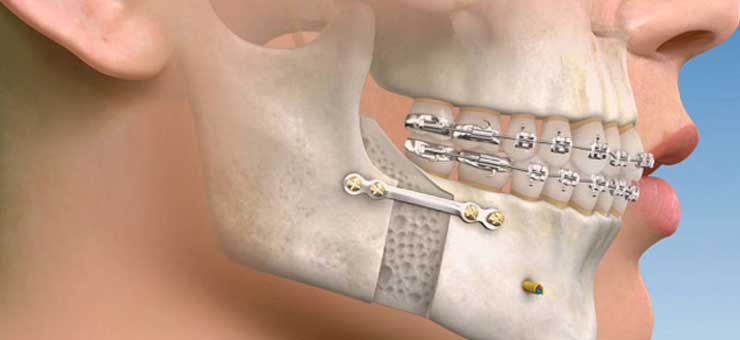

- The details of the surgery performed will depend on what you are having done and will be explained to you by your oral and maxillofacial surgeon.Surgery might aim to reposition part or all of the top and/or lower jaw.The surgeon gains access to the bones inside the mouth via the gums. Once the areas of bone have been revealed and loosened they are moved into a new position and fixed in position with small metal plates and screws, which usually remain in the bone. Sometimes these plates will be removed later, which will mean another operation. The jaw position is also maintained using a thin, clear plastic splint (or wafer), which sometimes remains secured to the lower teeth for some weeks. We use dissolving stitches to neatly close up the gums.